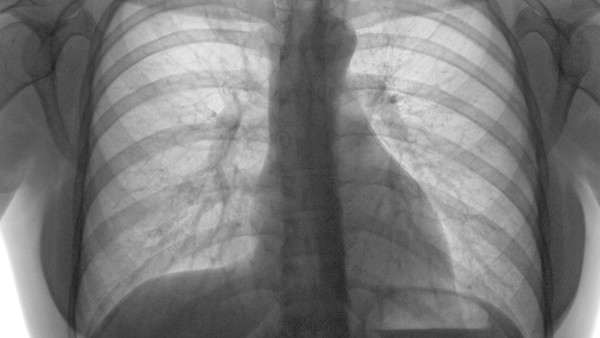

5、血气胸:肋骨骨折也有可能会导致胸腔部位受到损伤,会导致血液进入到胸腔之内,形成血气胸,可能会出现胸痛、呼吸困难,在正常走路时并没有明显症状,但是在躺下时,可能会对肺部组织造成压迫,影响到正常活动,建议选择胸腔闭式引流的方式,能够排出胸腔内的积血,能够改善呼吸功能。